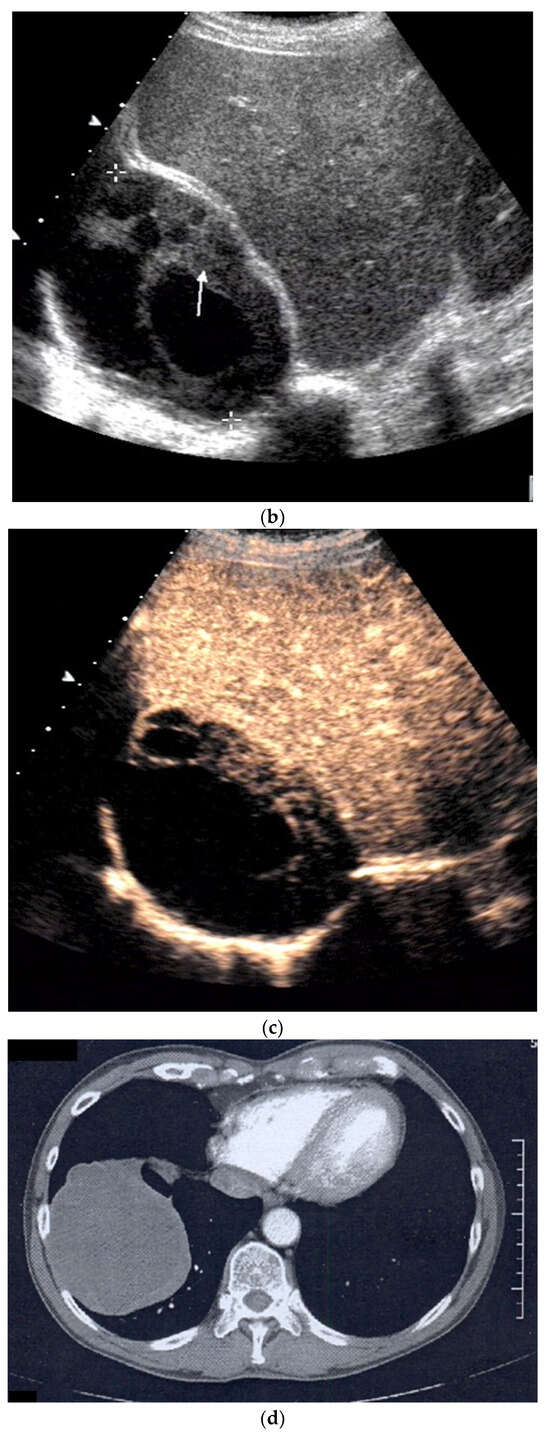

| Empyema | Hypoechoic thickened pleura, internal echos in the pleural effusion, hypoechoic pus, hyperechoic gas reflexes, fibrin strands, and chambering. In the phase of organization, thickened pleura, chambering of the pleural space. |

| Empyema necessitans | Exceeds the parietal pleura and infiltrates the surrounding soft tissue and chest wall muscles. |

| Tuberculous pleuritis | Pleura effusion with fibrin strands, pleural calcification, and thickening. Hypoechoic granulomatous inflammation and granulomas with hyper-enhancement on CEUS in thickened pleura. Hypoechoic caseous abscesses in thickened pleura, hypo- or nonenhanced, heterogeneously enhanced lesions, with contrast-enhanced septations and contrast-enhanced rim. |